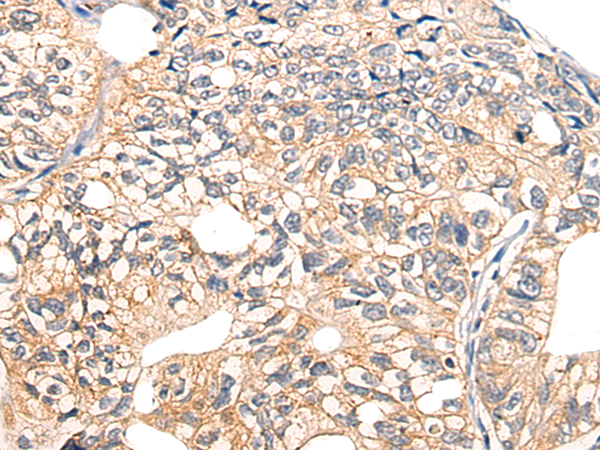

分类: 科研抗体货号: P13182别名: CIAB1; TAOS1; ORAOV1应用: IHC反应种属: Human